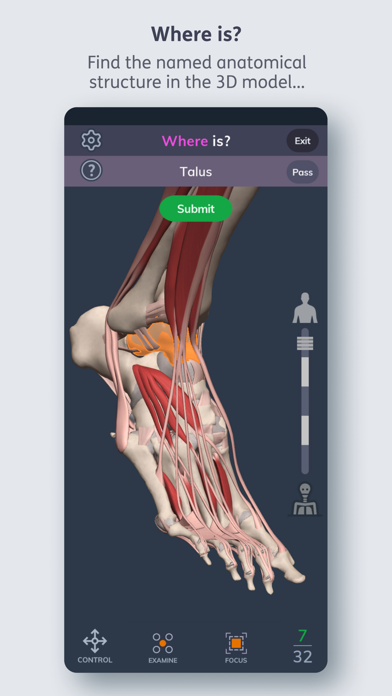

Primal's 3D Human Anatomy Quiz

Primal's 3D Human Anatomy Quiz is an app developed

by Pharma Intelligence UK Ltd.